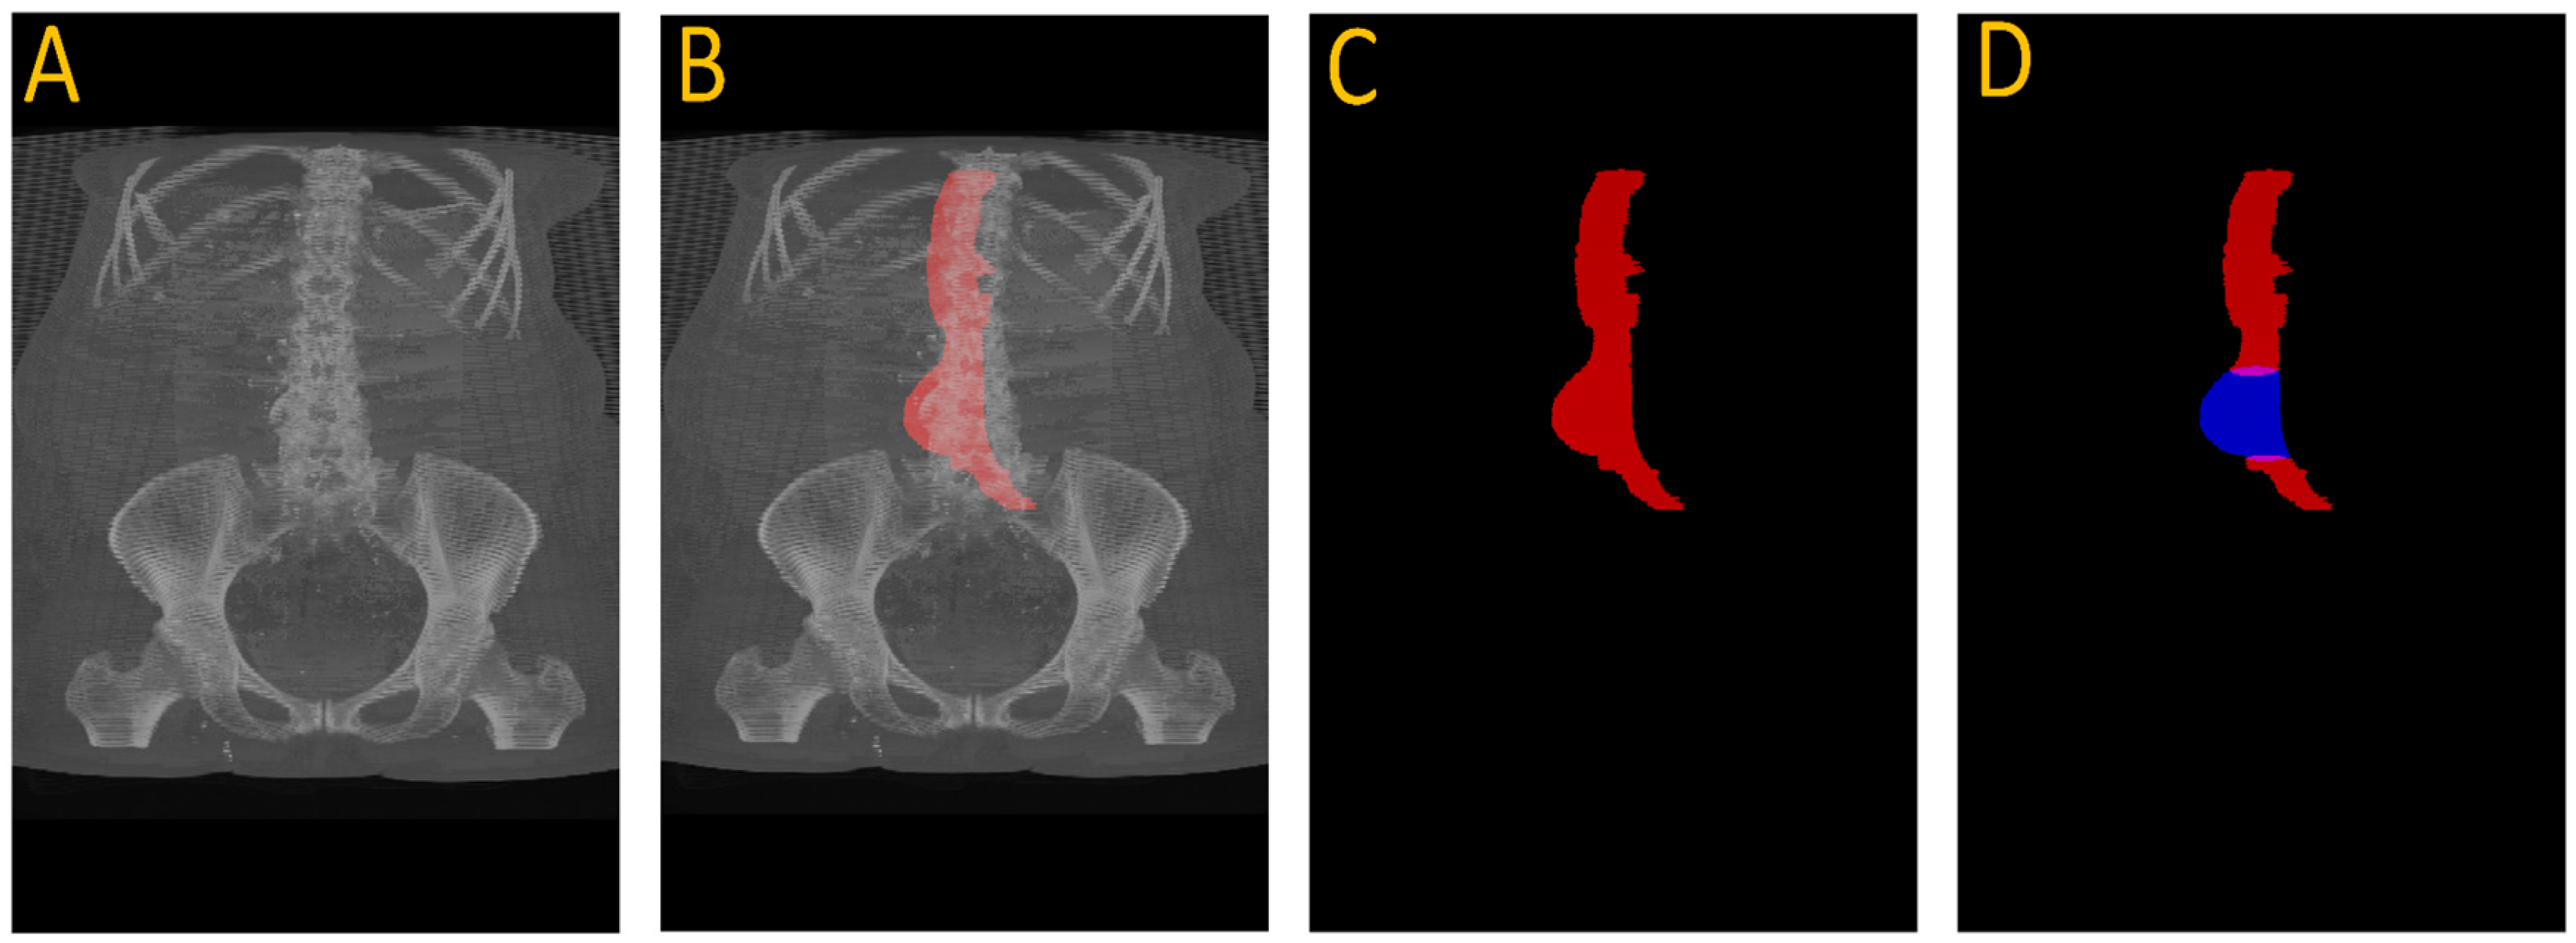

Despite its limitations, the UNet accurately localized normal aortic slices. We extracted the first slice with successful segmentation and established the center coordinates (x, y) of the aorta. These served as point prompts for the SAM2 model. Using point prompts from UNet, the SAM2 model tracked the aorta throughout the entire scan. It adapted its segmentation to changes in aortic shape, including aneurysmal regions. The result is a per-slice segmentation mask and a count of segmented pixels representing cross-sectional area.

Figure 3 illustrates this full pipeline. Panel A shows the original CTA scan, while B displays the complete aorta mask generated by SAM2 after propagation over the input image. C shows the segmented mask from SAM2 output and finally, panel D highlights the aneurysm region using the manual annotation, with red indicating normal aorta segment and blue denoting the aneurysm segment. This visualization demonstrates how UNet and SAM2 operate in tandem: UNet anchors the aorta in normal regions, and SAM2 tracks it seamlessly across the aneurysm segments for full-volume segmentation. Figure 4 provides a cross-sectional view at the aneurysm’s start and end boundary, further illustrating the model’s performance.

Figure 3. Full aneurysm segmentation pipeline. (A) Original CTA scan; (B) SAM2-generated aorta mask overlaid on the scan after propagation; (C) Binary segmentation mask produced by SAM2; (D) Manual annotation showing normal aorta (red) and AAA region (blue). The sequence shows how the proposed approach extracts an aneurysm despite having no aneurysm labels during training.